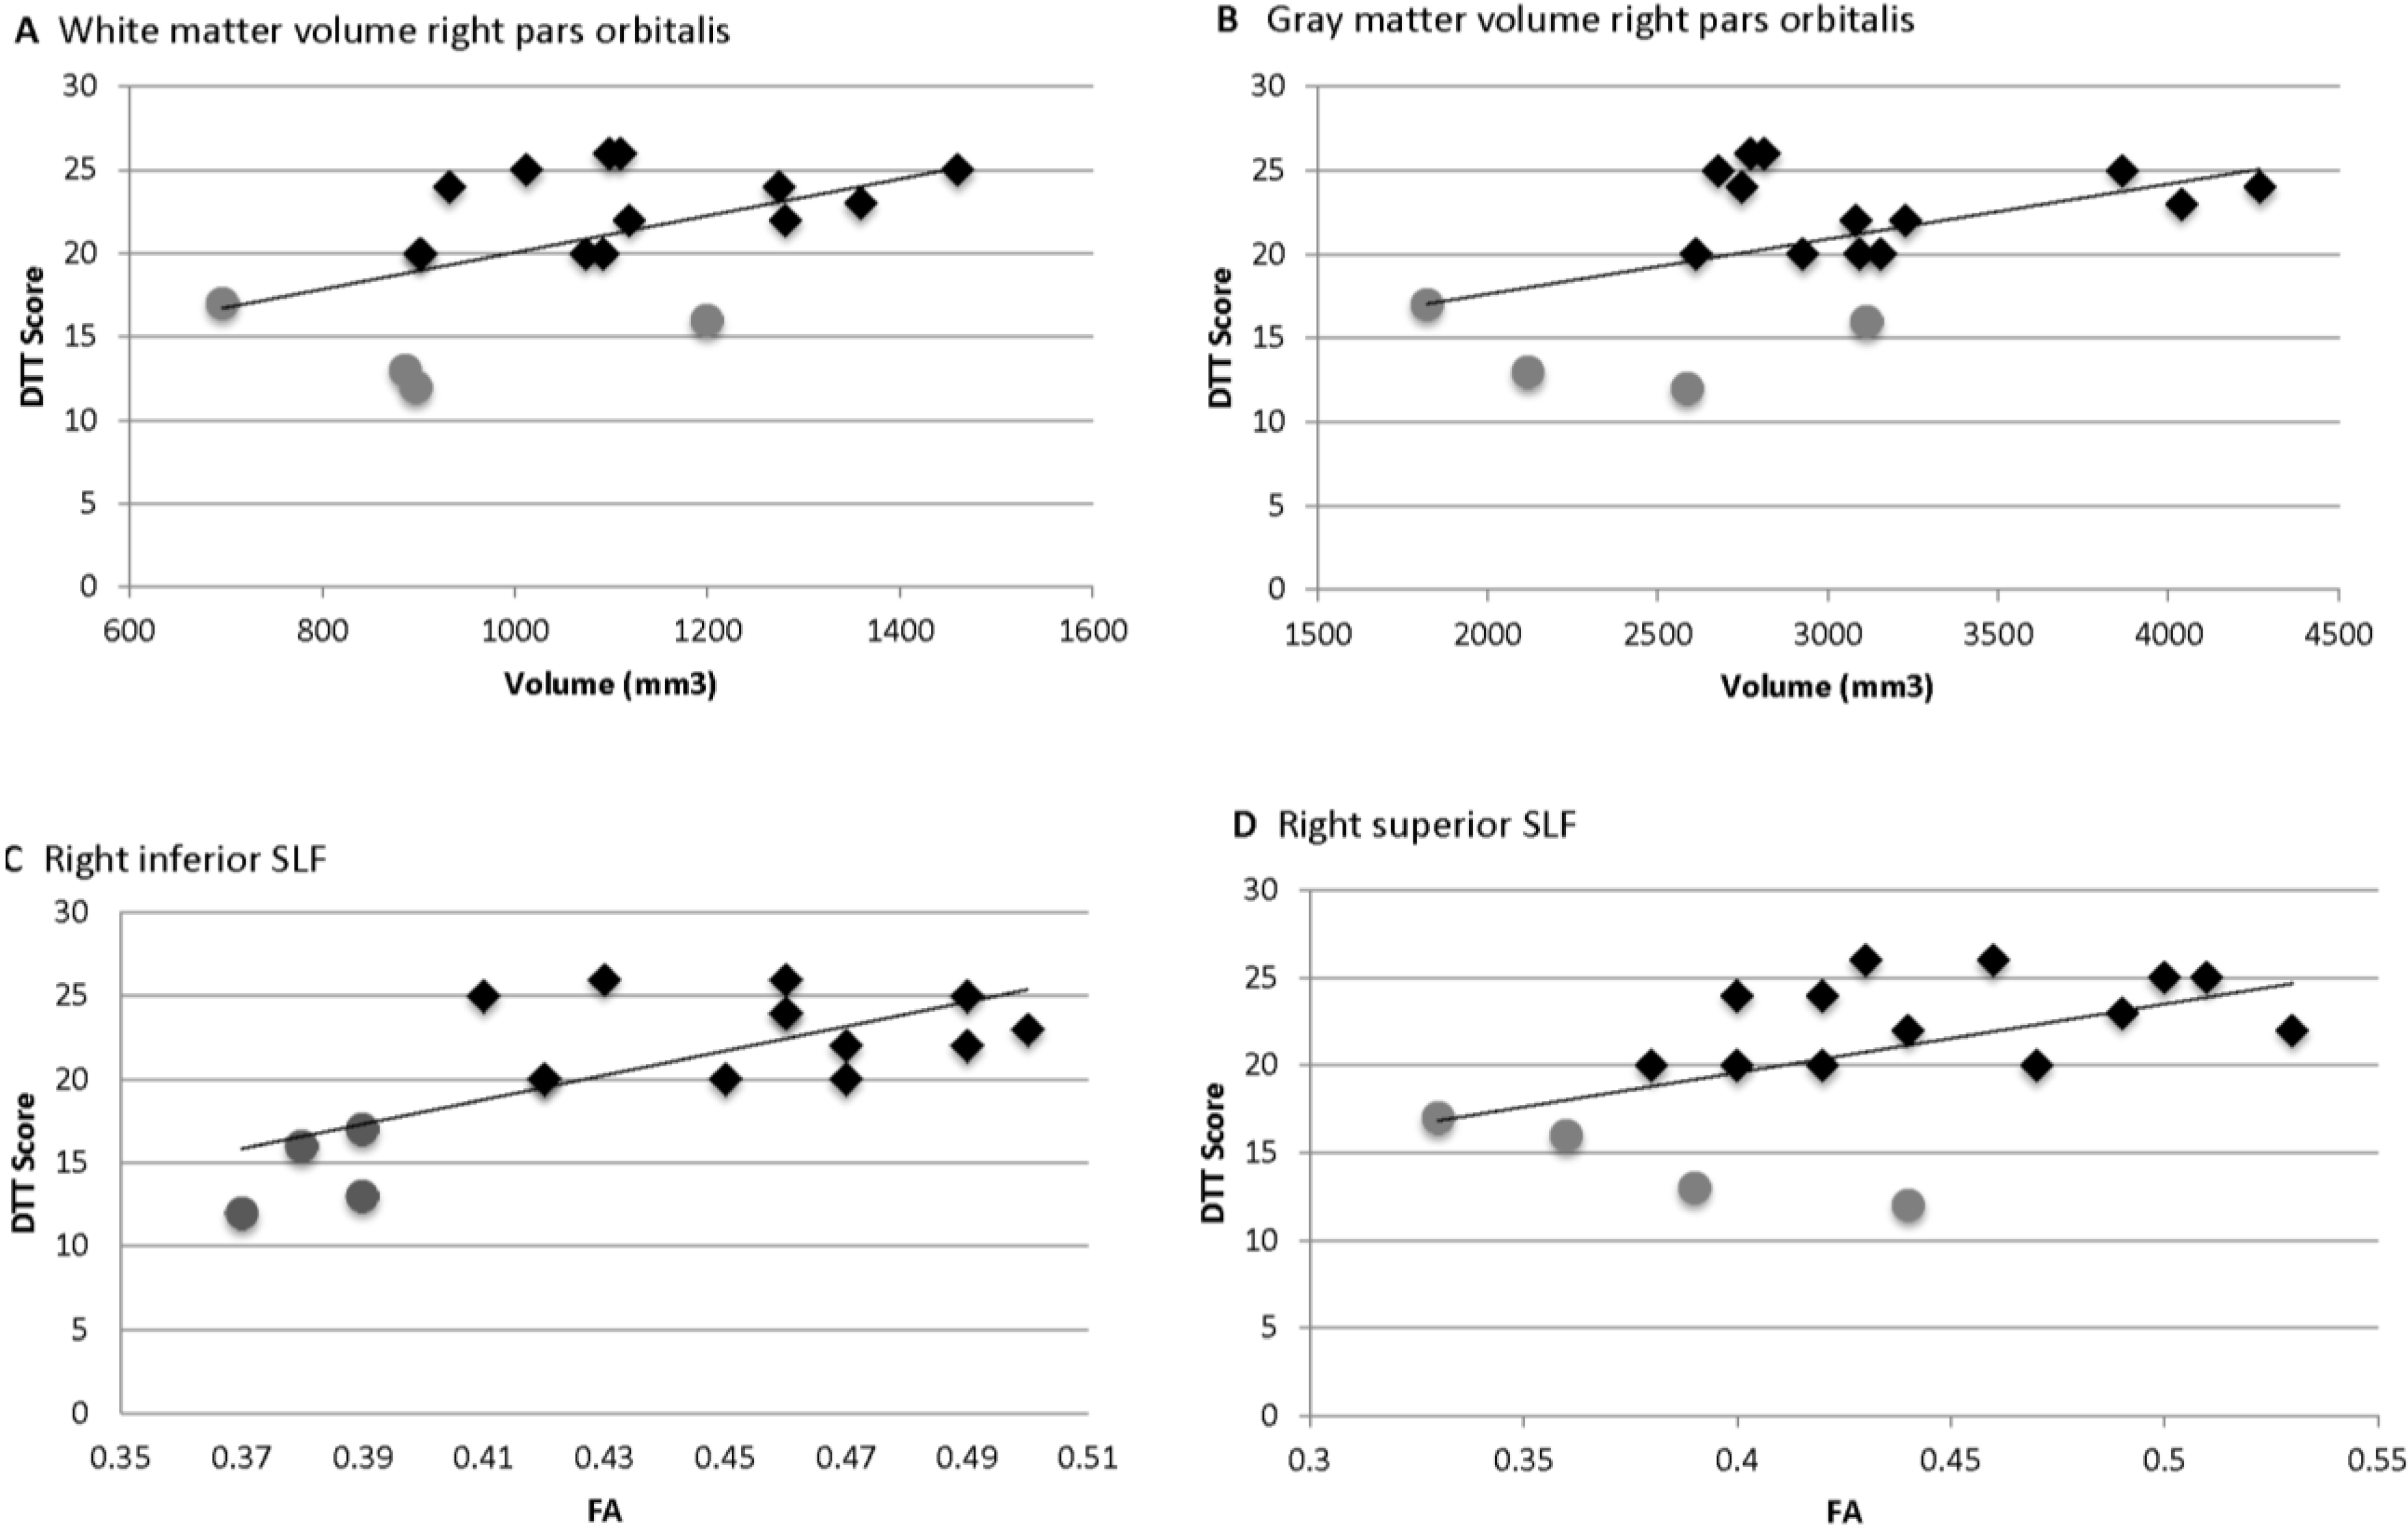

= Amusia. (A) DTT scores and white matter volume of right pars orbitalis (r = 0.507, p = 0.038); (B) DTT scores and gray matter volume of right pars orbitalis (r = 0.479, p = 0.052); (C) DTT scores and FA of right inferior SLF (r = 0.694, p = 0.002); (D) DTT scores and FA of right superior SLF (r = 0.506, p = 0.038).

= Amusia. (A) DTT scores and white matter volume of right pars orbitalis (r = 0.507, p = 0.038); (B) DTT scores and gray matter volume of right pars orbitalis (r = 0.479, p = 0.052); (C) DTT scores and FA of right inferior SLF (r = 0.694, p = 0.002); (D) DTT scores and FA of right superior SLF (r = 0.506, p = 0.038).

= Amusia. (A) DTT scores and white matter volume of right pars orbitalis (r = 0.507, p = 0.038); (B) DTT scores and gray matter volume of right pars orbitalis (r = 0.479, p = 0.052); (C) DTT scores and FA of right inferior SLF (r = 0.694, p = 0.002); (D) DTT scores and FA of right superior SLF (r = 0.506, p = 0.038).

= Amusia. (A) DTT scores and white matter volume of right pars orbitalis (r = 0.507, p = 0.038); (B) DTT scores and gray matter volume of right pars orbitalis (r = 0.479, p = 0.052); (C) DTT scores and FA of right inferior SLF (r = 0.694, p = 0.002); (D) DTT scores and FA of right superior SLF (r = 0.506, p = 0.038).